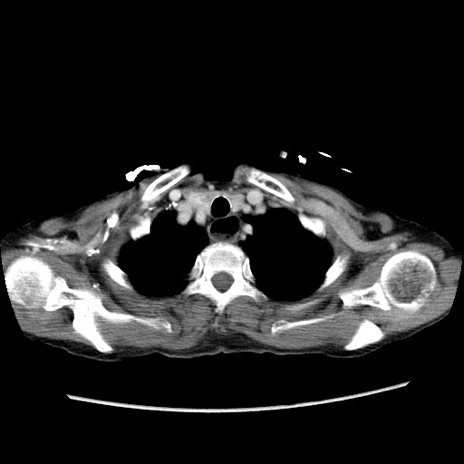

【症例】80歳代女性

【主訴】胸のつかえ感

【現病歴】約9時間前に食後から胸のつかえた感じあり、嘔吐あり、来院。

【既往歴】胃癌(全摘)、胆摘、虫垂炎

【身体所見】心窩部に圧痛あり、反跳痛なし。

【データ】WBC 5700、CRP 0.05